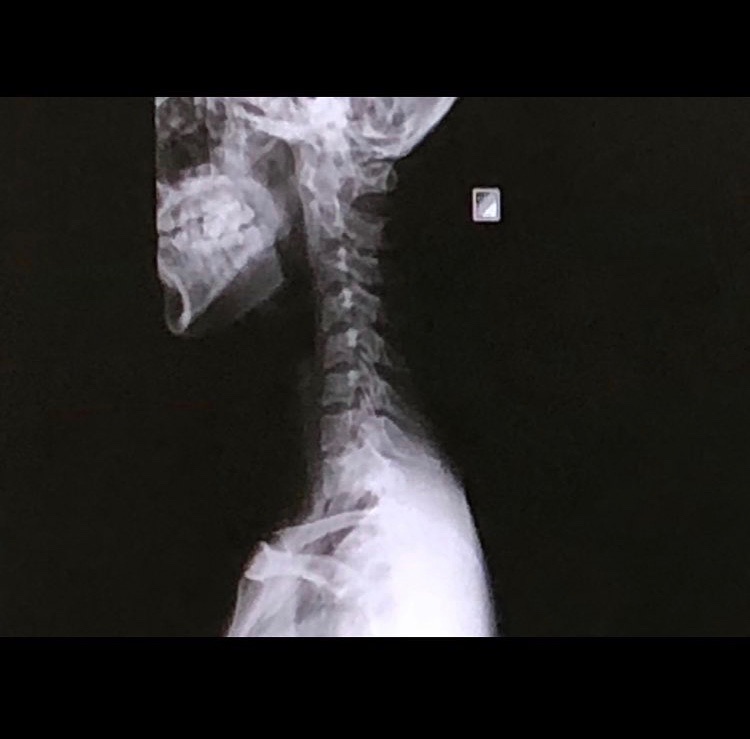

ストレートネック且つ後弯。

救急車を呼ぼうか迷ったほどの首の激痛から3日。ほぼ初めて整形外科に行きレントゲンを撮っていただきました。

知識の無い私ですら笑ってしまったほどのストレートネック。からの後弯。

骨自体に問題は無いようだったのでそこは一安心。